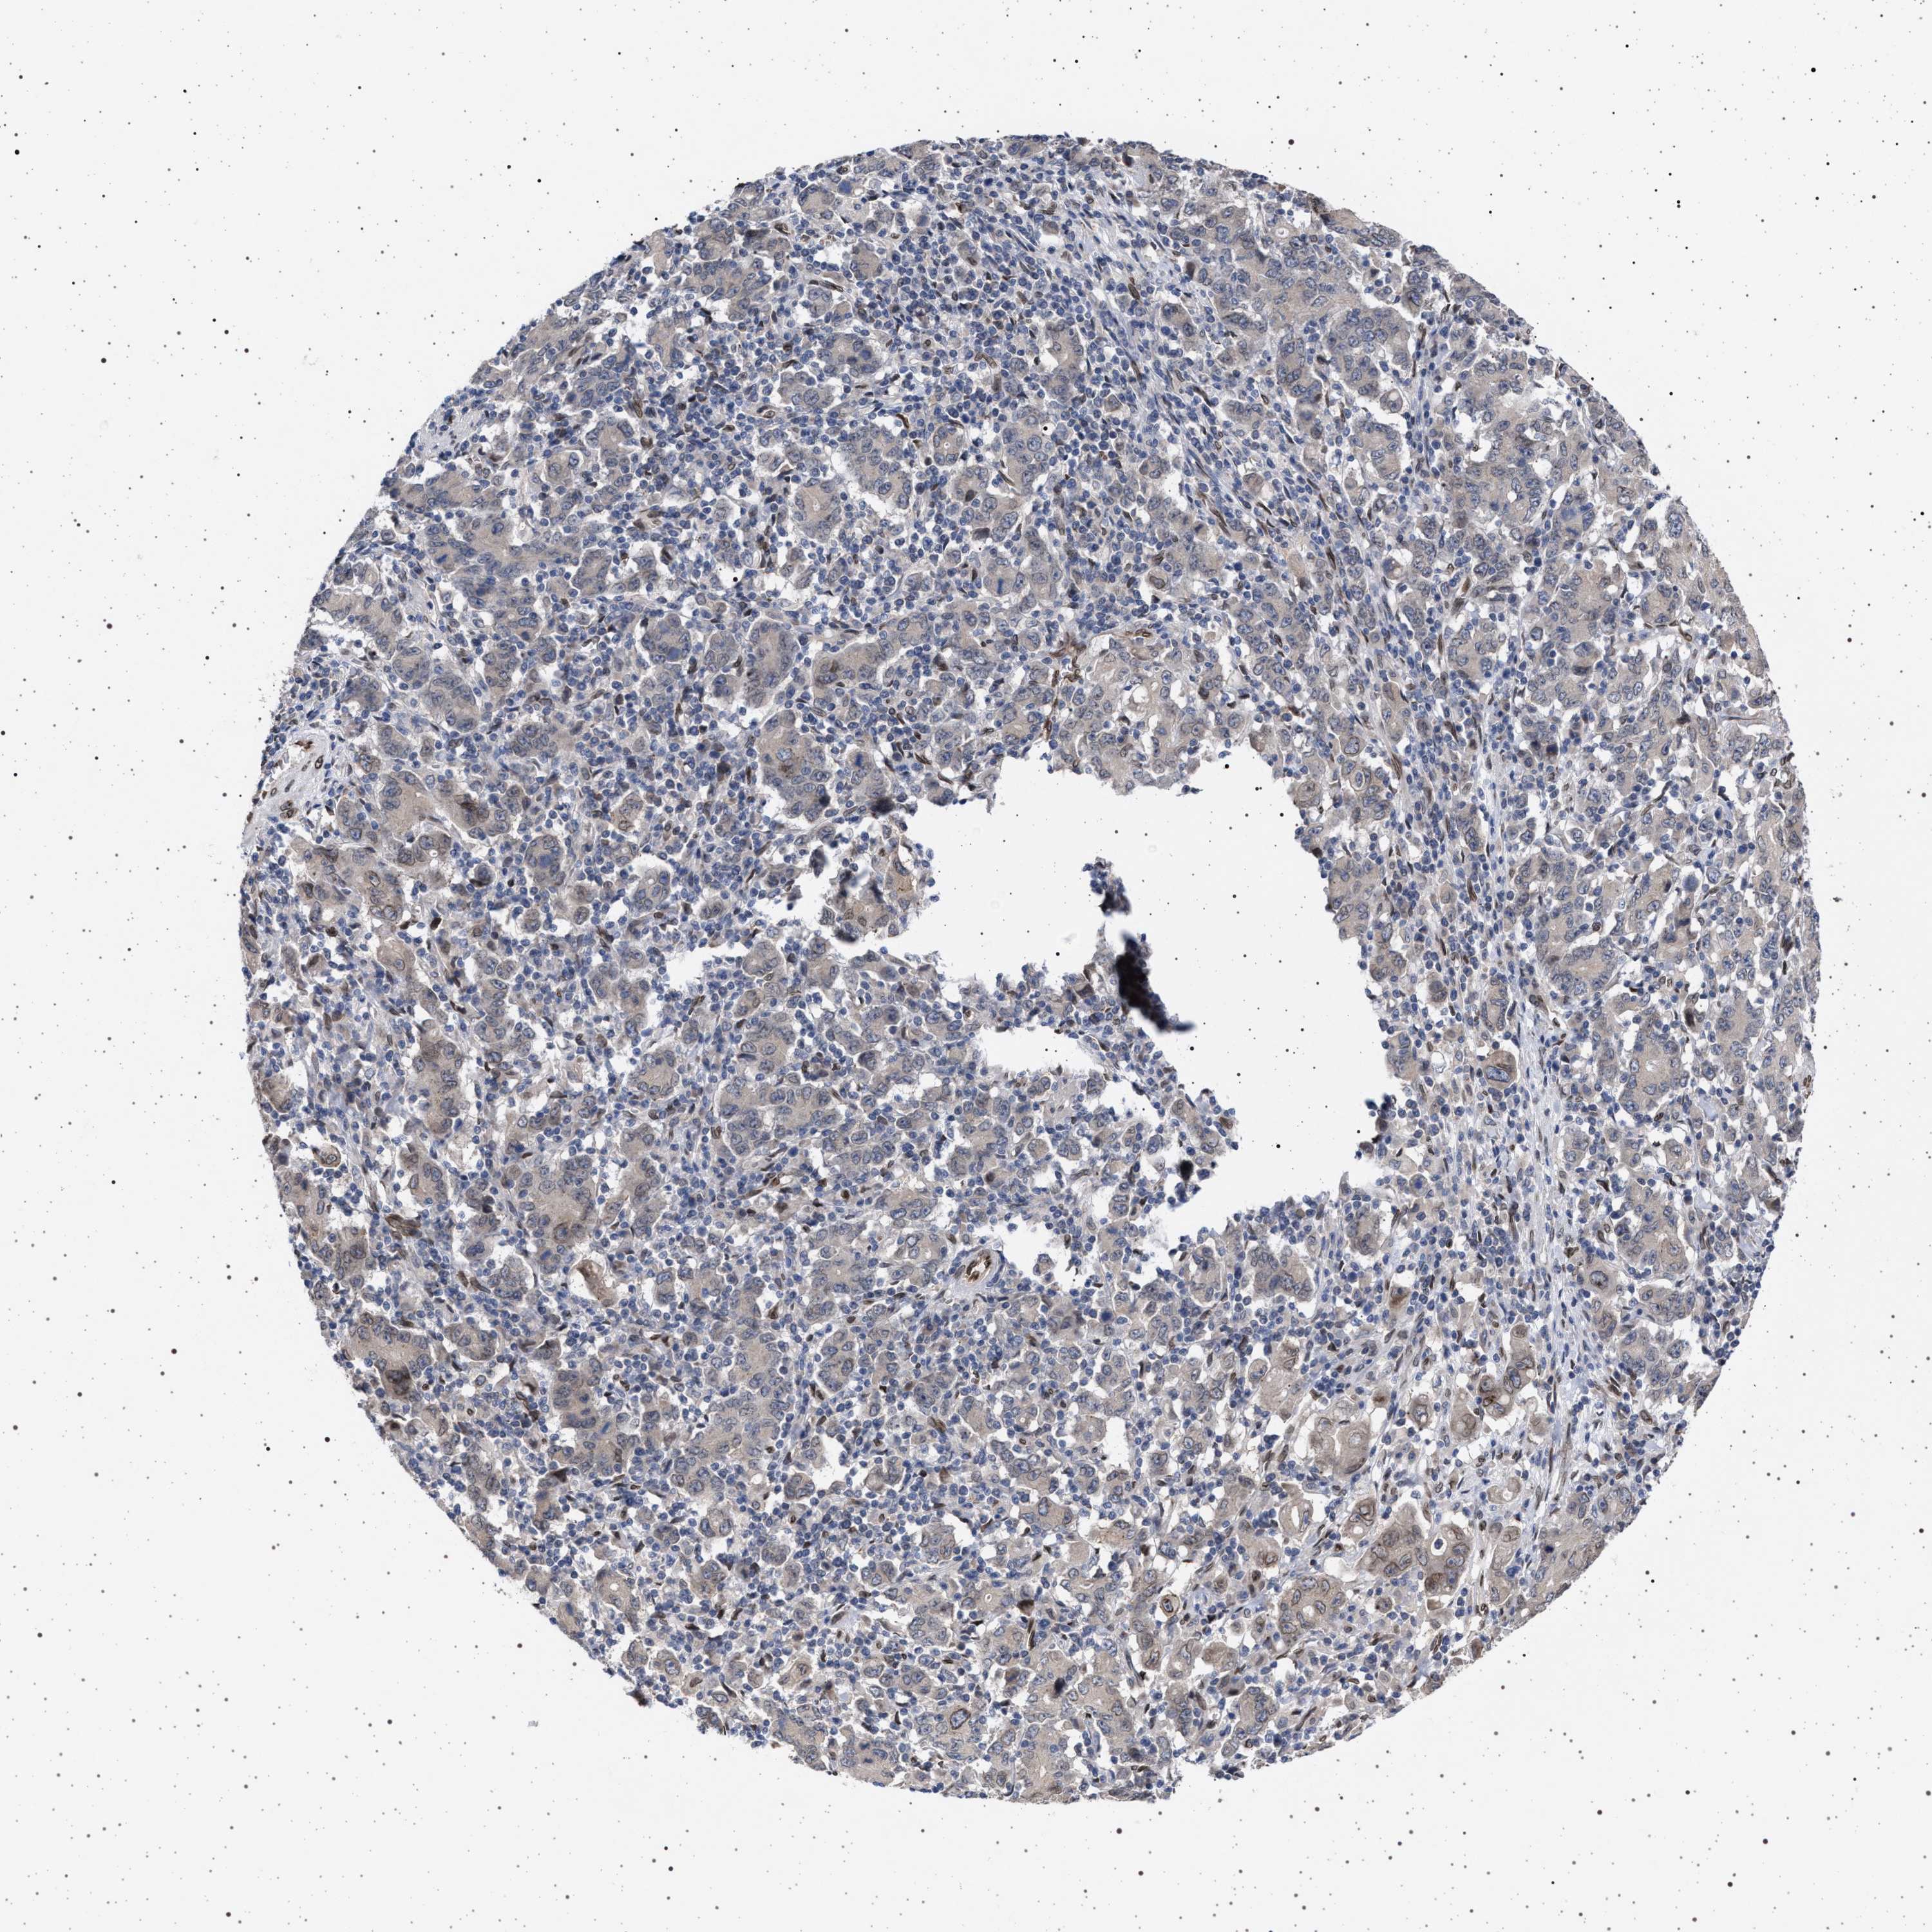

STOMACH CANCER - Protein expressioni

A mouse-over function shows sample information and annotation data. Click on an image to view it in a full screen mode. Samples can be filtered based on level of antibody staining by selecting one or several of the following categories: high, medium, low and not detected. The assay and annotation is described here.

Antibody stainingi

Antibody staining in the annotated cell types in the current human tissue is reported as not detected, low, medium, or high, based on conventional immunohistochemistry profiling in selected tissues. This score is based on the combination of the staining intensity and fraction of stained cells.

Each image is clickable and will lead to virtual microscopy that enables deeper exploration of all samples and also displays staining intensity scores, fraction scores and subcellular localization as well as patient and tissue information for each sample.

Adenocarcinoma, NOS